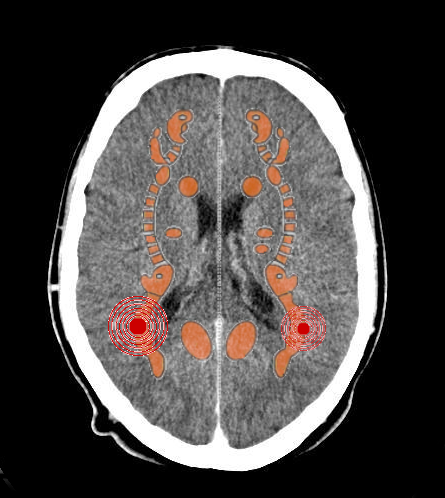

- Relè cerebrali: Due relè nella sostanza bianca cerebrale;

- Manifestazione: Megalomania. Vantarsi, farsi grandi, arroganza, comportamento egocentrico, auto-delirio.

In caso di coinvolgimento del miocardio e della parte muscolare del diaframma muscolare: Credersi in grado di fare ogni cosa

- Senso biologico: Se la persona si sente incapace, inadeguata tanto da non rimanergli altro che l'implosione e la morte, il superprogramma gli permette di risorgere dalle proprie ceneri e, millantando le proprie capacità e le proprie dotazioni, avere modo di tornare a essere qualcuno nel gruppo sociale che lo ha annichilito;

- Connessioni con il DSM: Questo quadro è compatibile con i Deliri, Disturbo Bipolare I, con il Disturbo da comportamento sociale disinibito, con il Disturbo della Condotta, con il Disturbo Anti-sociale di Personalità, con il Disturbo Narcisistico di Personalità;